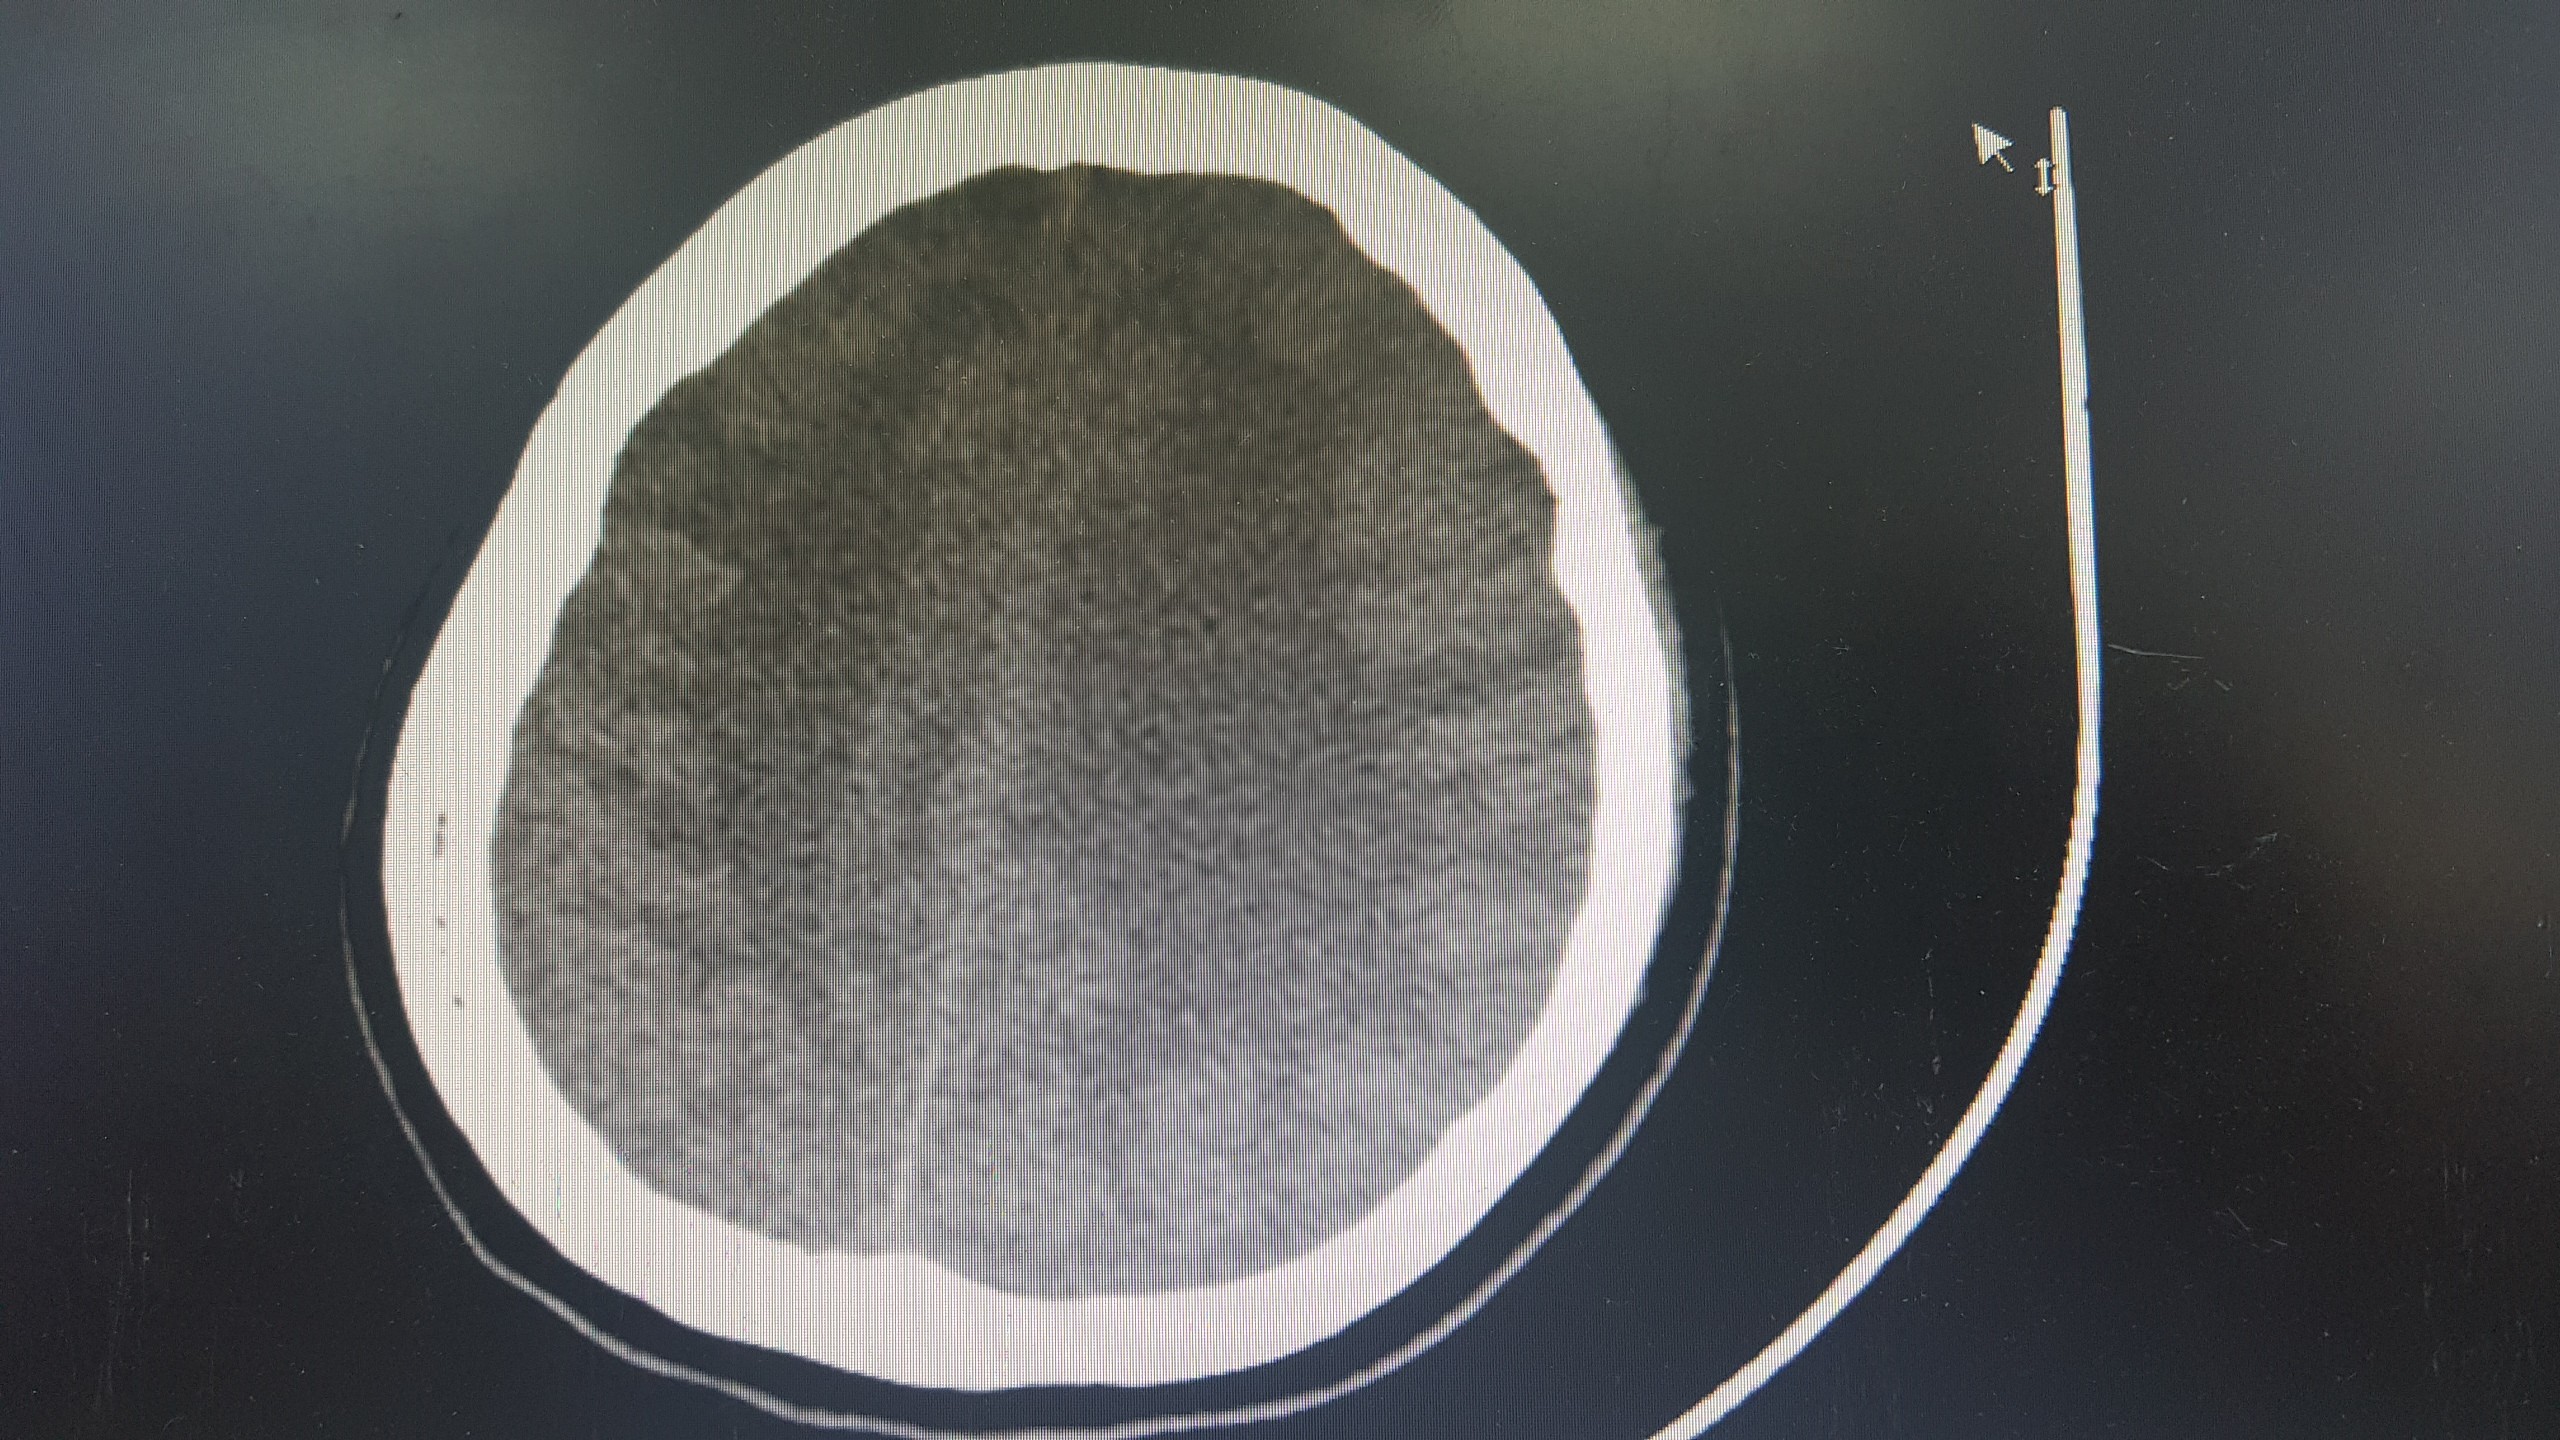

TS.BS. Nguyễn Trung Nguyên, Giám đốc Trung tâm Chống độc cho biết: Bệnh nhân đang trong tình trạng rất nguy kịch do tổn thương và suy nhiều cơ quan, trong đó nặng nhất là tổn thương não lan tỏa tại tất cả các vị trí. Trường hợp của bệnh nhân gần giống như ca đột quỵ não nhưng nặng hơn rất nhiều.

Nếu đột quỵ não chỉ gây tổn thương nhỏ ở một số vị trí thì ở trường hợp này là tổn thương gần như toàn bộ não. Ngoài ra, bệnh nhân còn bị tổn thương và suy tim nặng, suy thận, tổn thương gan. Tiên lượng điều trị và hồi phục của bệnh nhân là vô cùng dè dặt.

Ảnh chụp não bị tổn thương của bệnh nhân. Ảnh: BVCC